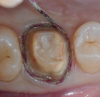

Figure 3: Retraction cord placed for a single-unit crown preparation. Note the 360º visibility of the cord.

Figure 3

Figure 4: Impression made of the tooth in Figure 3. Note the flash is consistently 1-mm deep and 1-mm wide, reflecting the precise placement of the retraction cord prior to the impression.

Figure 4

Retraction cords are available with and without vasoconstrictors; the author prefers stiffer ones and using the two-cord method described below. They are usually placed completely around the prepared tooth and placed at the top of the sulcus, so the entire diameter of the cord is visible and the clinician can ascertain that the flash of the light-body material will have the desired 1-mm depth and 1-mm thickness (Figure 3 and Figure 4). If placed too deeply in the sulcus, the tissue can partially cover the cord and prevent the light-body material from correctly recording a correct impression.